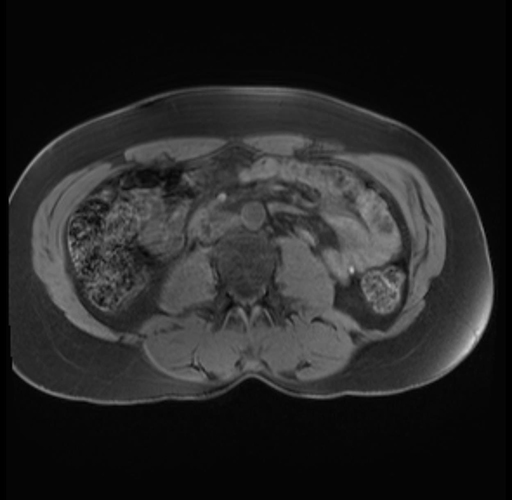

Imaging Analysis

Look through the patient's CT scan to identify any areas of concern for the necessary procedure.

Based on your CT findings, which issue(s) are present and would give reason for "planned slowing down moment(s)" in this case?

Considering a standard distal pancreatectomy procedure, what step(s) of the operation would you do differently in this case?